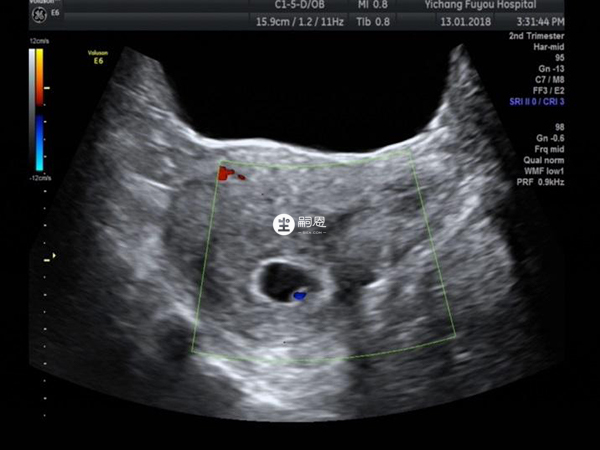

孕妇的早孕超声作用是非常多的,它可以证实宫内妊娠、诊断多胎妊娠、评估孕周、计算预产期、了解胚胎/胎儿情况、查找早孕出血原因等等,它可以对胎儿的双顶径、头围、腹围、股骨进行测量,测量以后估测孕周以及预产期,下面就为大家详细介绍早孕超声准确估计妊娠时间和预产期的方法:

早孕超声准确估计妊娠时间是利用孕天数=平均孕囊直径mm+30,或胚芽长度mm+42;孕周数=胚芽长度cm+6.5(+/-4天)来计算的。而预产期的是根据超声中孕囊的大小或头臀径的长度来计算,再结合末次月经综合判断,预产期的计算公式就是最后一次月经来潮的月份减掉3(不足者加上9)或月份直接加9也可,日数加上7,即为预产期。

月经周期规律的患者直接使用末次月经来计算即可,但如果月经不准,就需要看早孕超声结果判断,先判断妊娠时间再计算出预产期,但需要注意要在12周以前才行,因为12周以后胎儿发育有快有慢,超声推算就不准了。